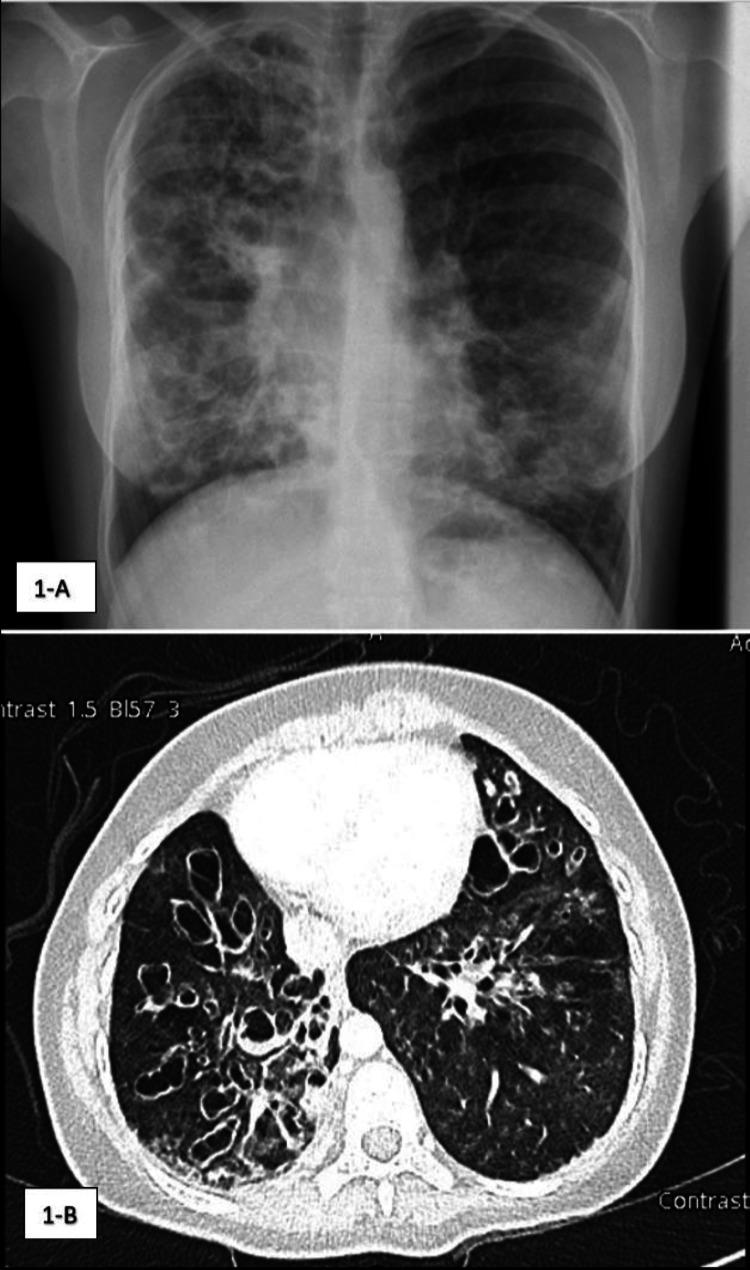

Primary ciliary dyskinesia (PCD) is a heterogeneous autosomal recessive disease marked by organ lateralization in 50% of patients, chronic sinopulmonary disease, infertility in men, and neonatal respiratory distress. Respiratory control cells contain in their apical cytoplasm, which is necessary for the development of multiciliate cells, basal body amplification, and migration. Reduced generation of multiple motile cilia, a rare form of PCD, has been linked to gene abnormalities Individuals with mutations have been reported to suffer from severe lower respiratory infections that cause progressive impairment of lung function. For the first time, we describe the (c.258 262dup.p, Gln88argfs*8 Homozygous) gene mutation in an Indian consanguineous family that resulted in severe PCD.

原发性纤毛运动障碍(PCD)是一种常染色体隐性遗传病,具有异质性,其特征为50%的患者出现器官定位异常、慢性鼻窦肺部疾病、男性不育以及新生儿呼吸窘迫。呼吸控制细胞在其顶端细胞质中含有(某种物质),这对于多纤毛细胞的发育、基体扩增和迁移是必需的。多根活动纤毛生成减少是PCD的一种罕见形式,它与(某个)基因异常有关。据报道,携带(该)基因突变的个体患有严重的下呼吸道感染,可导致肺功能进行性损害。我们首次在一个印度近亲家庭中描述了(某个基因)(c.258 262dup.p,Gln88argfs*8纯合子)基因突变,该突变导致了严重的PCD。